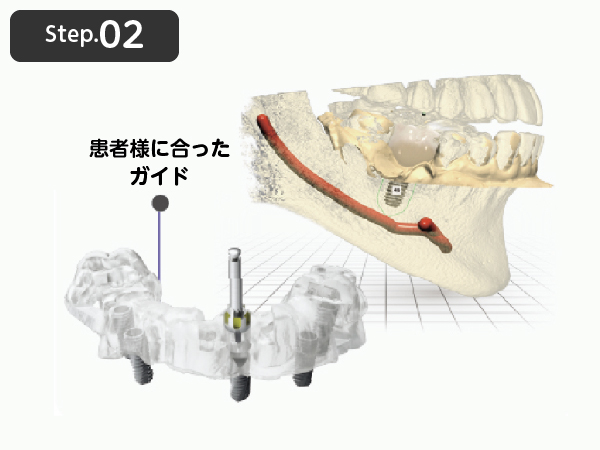

サージカルガイドについて

デジタルシミュレーションを行うと、CTで撮影したデータを元にマウスピース型のサージカルガイドが作成されます。サージカルガイドには、インプラントの埋入位置や深さ・角度など、正確な手術を行うために重要な情報が詰まっています。そのため、インプラント手術時にサージカルガイドを装着できるようになったことで、治療計画から狂いのない位置にインプラントを埋入することが可能となりました。

STEP.02

デジタルシミュレーションで

ガイドを作成